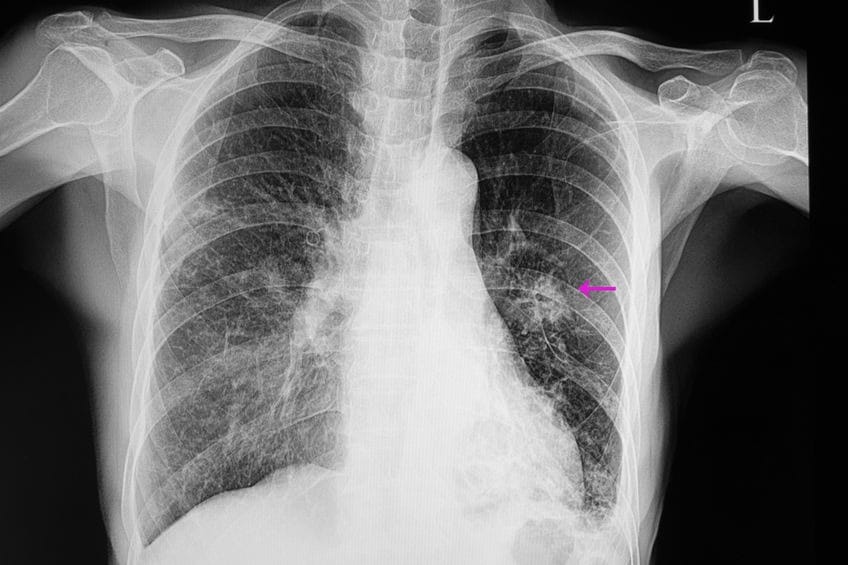

ERKEN TANI 5 YILLIK YAŞAM ŞANSINI ARTIRIYORAkciğer kanserinde erken tanı, tedavi başarısını önemli ölçüde artırdı ve yaşam süresini uzattı. Erken evrede tanı alan hastalarda 5 yıllık sağkalım oranı yüzde 60’ın üzerine çıkarken, ileri evrelerde bu oranın yüzde 10’un altına düştüğü belirtildi.

YÜKSEK RİSKLİLER İÇİN AKCİĞER KANSERİ TARAMA ÖNERİSİTürkiye’de akciğer kanseri için belirlenmiş bir tarama programı bulunmadığını ifade eden Marım, uzun süre sigara içenler, pasif içiciler ile mesleksel ve çevresel maruziyeti olan yüksek riskli bireylerde düşük doz bilgisayarlı tomografi ile yıllık taramanın erken tanıda en etkili yaklaşımlardan biri olduğunu vurguladı.